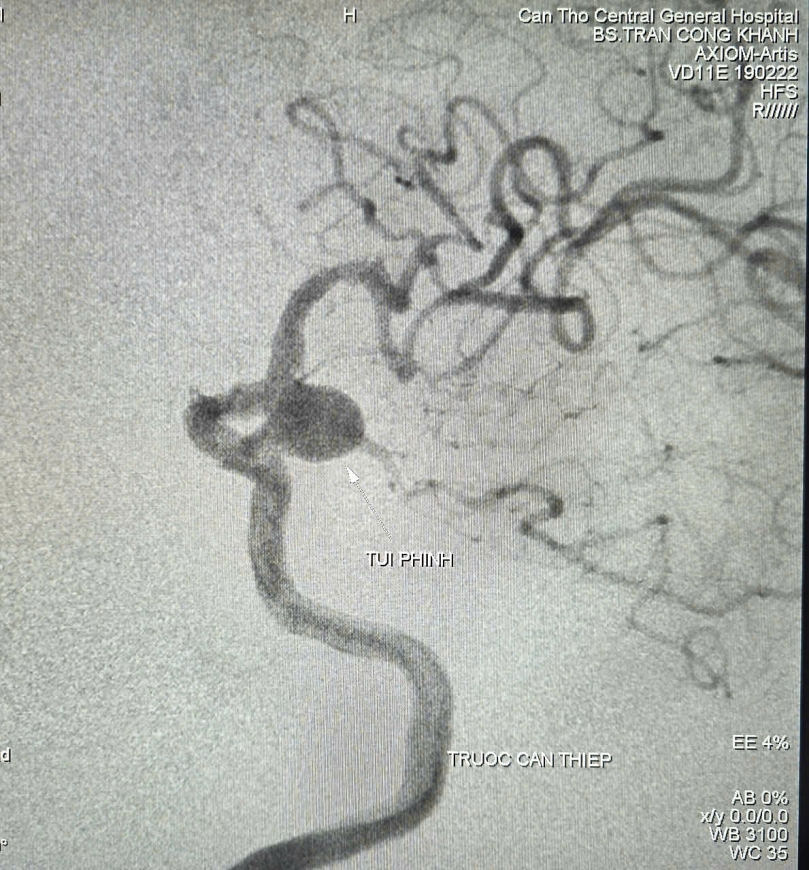

Bệnh nhân là cụ bà L.T.T., 90 tuổi, ngụ tại TP. Cần Thơ, được người nhà đưa đến bệnh viện lúc 7 giờ sáng ngày 16/8 trong tình trạng huyết áp cao (180/90 mmHg), đau đầu, nói chuyện được khó nghe. Bệnh nhân có tiền sử tăng huyết áp – nhồi máu nảo. Bệnh nhân được nhập khoa Đột quỵ để theo dõi và điều trị. Kết quả chụp cắt lớp vi tính và cộng hưởng từ cho thấy nhiều tổn thương cũ vùng não, túi phình đoạn gốc động mạch cảnh trong - thông sau bên trái, kích thước 9,2mm x 12mm, túi phình đang phát triển qua thời gian theo dõi (nguy cơ vỡ trong 5 năm khoảng 17.8%, ước lượng theo thang điểm PHASE 12 điểm).

Sau khi hội chẩn đa chuyên khoa và dựa trên các khuyến cáo, cân nhắc giữa lợi ích và nguy cơ, ê-kíp quyết định tiến hành chụp mạch số hóa xóa nền (DSA) và can thiệp nội mạch nút túi phình, giúp bệnh nhân hạn chế nguy cơ vỡ gây đột quỵ, xuất huyết.

BS.CKII. Trần Công Khánh, Phó Trưởng khoa Chẩn đoán hình ảnh, Bệnh viện Đa khoa Trung ương Cần Thơ cùng ê-kíp thực hiện cho biết, các bác sĩ đã luồn vi ống thông siêu nhỏ đến vị trí túi phình và tiến hành thả 04 vòng xoắn kim loại (coils) vào trong lòng túi phình. Kết quả chụp kiểm tra ghi nhận: Túi phình được tắc gần hoàn toàn, dòng máu lưu thông ổn định.

Hình ảnh túi phình mạch não trước khi can thiệp